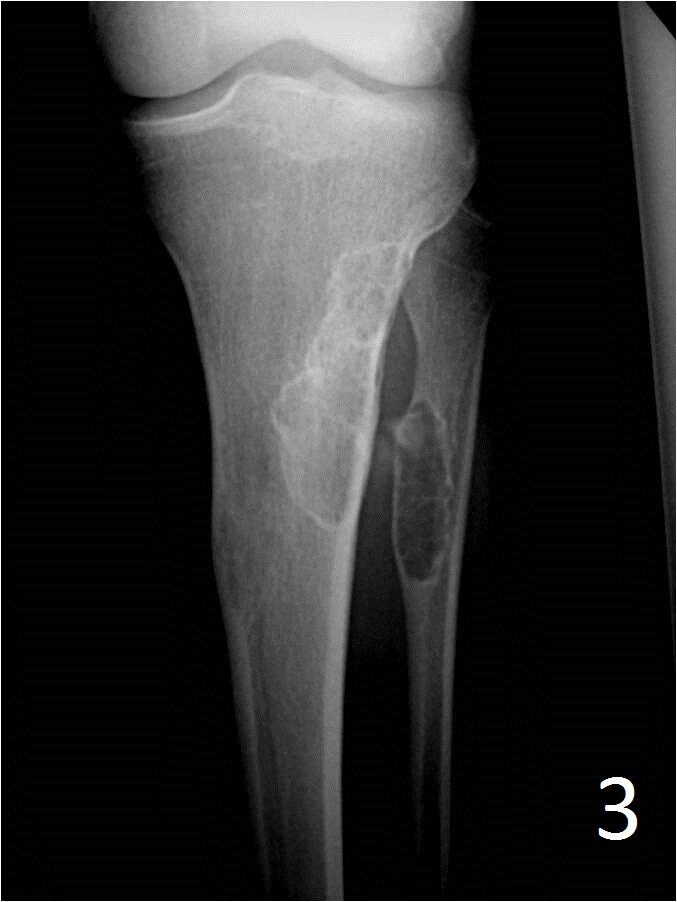

• New bone fills the defect and in some instances is denser than adjacent cortical bone leaving a residual “scar” on an xray, CT or MRI

Fig. 3: AP xray of tibia-fibula shows a healed (ossified) NOF of the proximal tibia and fibula.